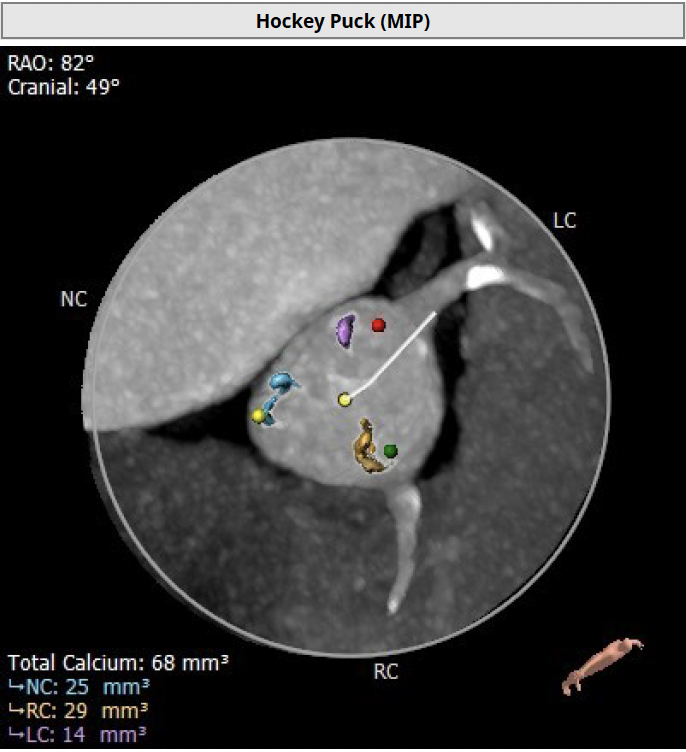

钙化积分68mm³

右冠

术前预案